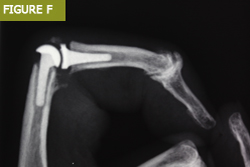

Parmak eklemi implantları için kullanılan malzemeler silikondan çeşitli sentetik plastik ve metal alaşımlarına kadar değişebilir (Şekil C). Kullanılan malzeme ve implant, ilgili eklem, hasta gereksinimleri ve mevcut cerrahi uzmanlık gibi çeşitli faktörlerle birlikte altta yatan patolojiye bağlıdır.

Parmak eklemi değiştirme implantları artık tüm parmak eklemleri için mevcuttur:

El bileği artroplastisinde çeşitli implant modülleri de kullanılmıştır: